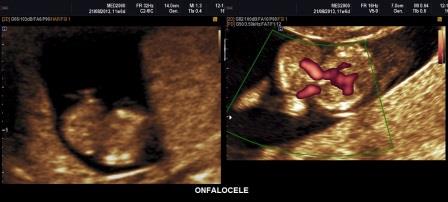

ONFALOCELE

E'

un difetto di chiusura della parete addominale in cui erniano l'intestino e/o

il fegato contenuti in una sacca composta da peritoneo parietale e amnios. Il

cordone ombelicale si inserisce all'apice della sacca. L'onfalocele viene

classificato in due distinte varietà anatomiche che hanno una differente

embriogenesi e prognosi anche in rapporto all'epoca gestazionale di

osservazione: onfalocele con fegato erniato ed onfalocele con solo intestino

erniato. Nei casi di presenza del fegato nella sacca non è possibile la

risoluzione. Se nella sacca è presente solo intestino è possibile la

risoluzione nel primo trimestre e non nel secondo.

Diagnosi Ecografica

La

diagnosi ecografica si basa sulla presenza, dopo la 12a settimana, di una

formazione grossolanamente rotondeggiante, rivestita da membrana, in diretta

continuità con la parete addominale; tipicamente il cordone ombelicale si

inserisce sulla parete dell'onfalocele. A

volte, nella sacca, è presente ascite; in circa 1/3 dei casi è presente

polidramnios. Prima della 12a settimana di gestazione un onfalocele può essere

diagnosticato con certezza solo se contiene il fegato: in questo caso l'aspetto

dell'onfalocele è tipicamente ecogeno. Se ad erniare è invece l'intestino

potrebbe trattarsi di una erniazione fisiologica e bisogna quindi attendere il

limite delle 12 settimane compiute per essere certi della diagnosi.